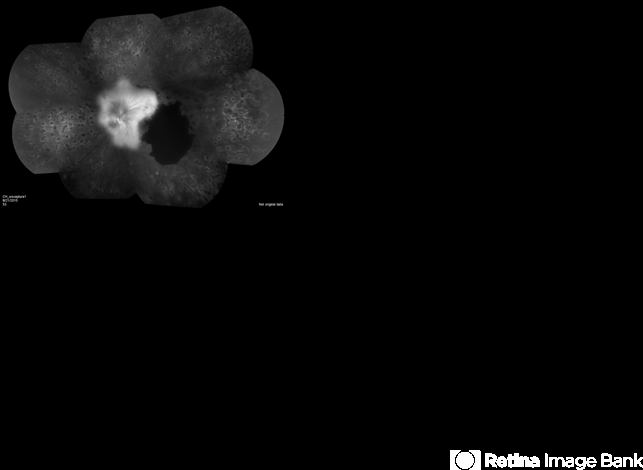

- proliferative diabetic retinopathy (PDR), retinal hemorrhage, pan-retinal photocoagulation (PRP)

- Proliferative diabetic retinopathy with neovascularization of the disc, hemorrhage and pan-retinal photocoagulation.